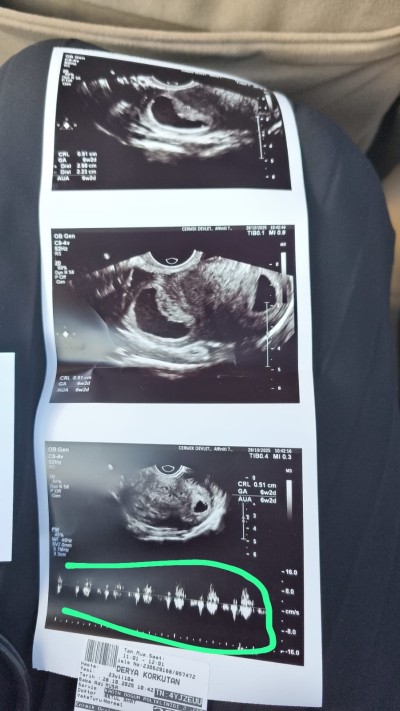

Merhabalar arkadaşlar, dün doktora kontrole gittim. Alttan ultrason ile bakıldı, bebeğim görüldü ve kalp atışı duyuldu. Çok şükür, çok mutluyum. Doktoruma, başka bir doktorun kanama alanım olduğunu söylediğini söyledim. Doktor hanım, kanama alanından ziyade kistin var dedi. 5 cm büyüklüğünde keseden uzakta, vücudunun bunu atmaya çalışıyor, o yüzden karın ağrıların olabilir dedi. Tecrübesi olan var mı?

Gebelik haftası 6+2